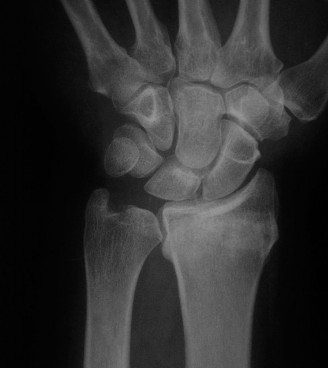

However, plain films are notoriously inadequate for assessing fracture union or complex comminution. As demonstrated in the clinical scenario, when a patient returns at 8 weeks post-injury and the clinician must determine whether the fracture has definitively healed, a Computed Tomography (CT) scan is the gold standard. CT scans oriented along the longitudinal axis of the scaphoid provide unparalleled visualization of trabecular bridging. A fracture is generally considered healed when greater than 50% trabecular bridging is observed across the fracture site.

1. Guide Wire Placement: A 0.045-inch K-wire is advanced from the proximal to the distal pole (or vice versa) under strict fluoroscopic guidance. The wire must be positioned in the central-central axis of the scaphoid on both PA and lateral views. Eccentric placement significantly reduces the biomechanical strength of the construct.

4. Confirmation: Fluoroscopy is utilized in multiple planes to confirm that the screw is entirely intraosseous and that no threads are proud within the radioscaphoid or scaphotrapezial joints.